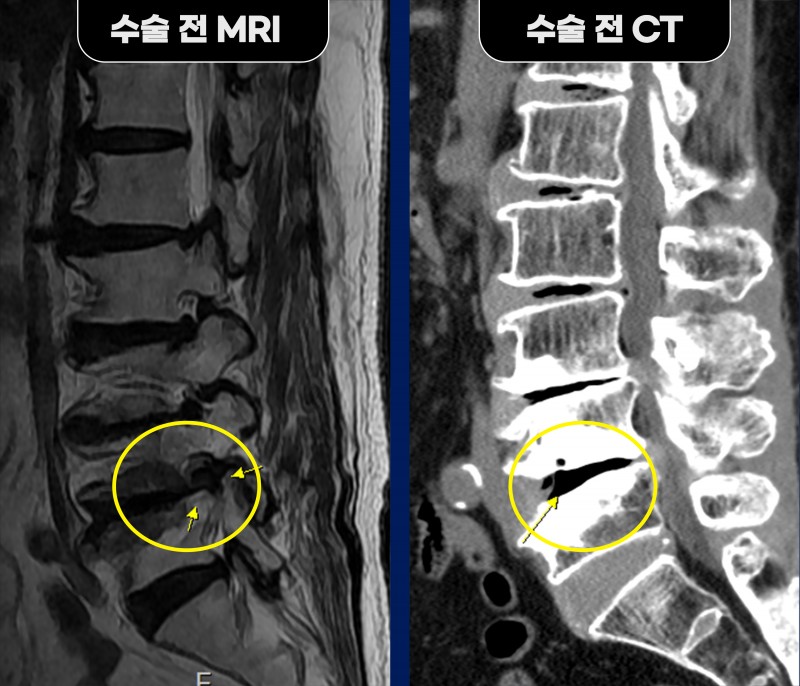

MRI 검사에서 특히 요추 4/5번 우측 추간공이

거의 막혀 신경이 심하게 압박된 소견이 확인되었고,

디스크 소실과 퇴행성 측만증, Modic change가 동반되어

일반적인 유합술은 부담이 큰 상황이었습니다.